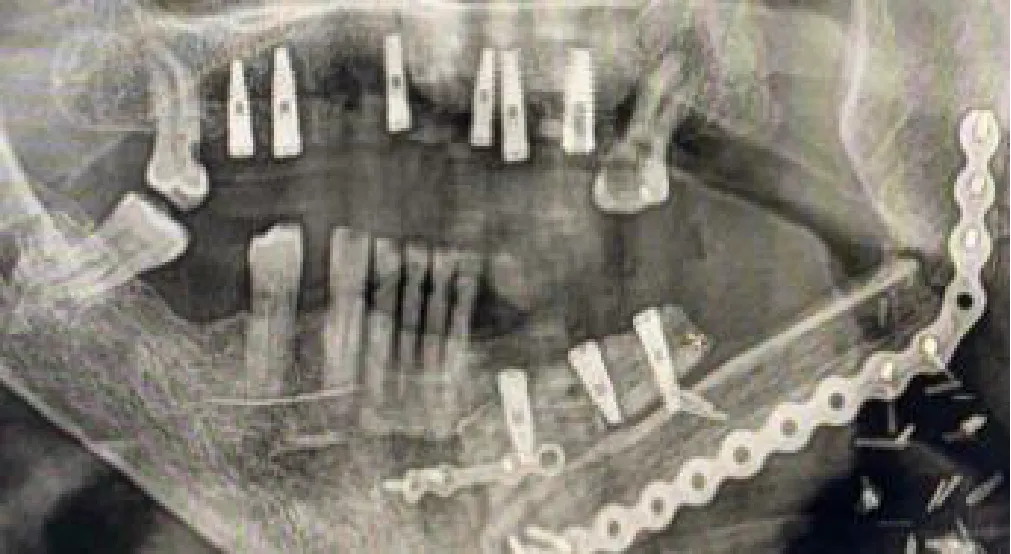

Therefore, for the subsequent seven cases, rigid resin tooth-supported guides were designed with 3D CAD (Blue Sky Bio software) and manufactured by 3D printing technology, seeking intraoperative stability. With this approach, the 3D-printed surgical guide provided excellent stability and was also used for intraoperative registration, avoiding the need for anatomical landmarks. For that purpose, the 3D CAD conventional rigid guide design was imported in Meshmixer software (Autodesk Inc., San Rafael, CA, USA) for design modifications. Several pinholes were added to the surgical guide surface to be used as reference landmarks during patient-to-image registration (Figure 3A). A specifically designed socket was also included to attach the dynamic reference frame during navigation or a 3D-printed marker during AR visualization. This socket was positioned on the same jaw as the planned implant but on the opposite side of the arch to avoid interference with the surgical instruments (Figure 3B). In general, our rigid guides were designed with a 9- to 12-mm offset between implant head and surgical guide for a 23- or 28-mm drill length. In addition, guiding tubes with a 5.2-mm diameter without metallic sleeves were included to mark the trajectories of the defined implants. Surgical guides were manufactured by the stereolithographic technique with a Formlab Form 2 3D printer and using BioMed Clear V1 biocompatible resin (Formlabs Inc., USA). Finally, surgical guides’ stability was evaluated by fitting them on the cast models and on the patient before surgery. With the advantageous rigid guide in place, holding the registration tracers, we could consider dynamic- or static-guided surgery, augmented reality, or a combination of all of them.

To overcome this stability problem, we introduced the sCAIS in our study, based on a 3D-printed teeth-supported surgical guide that not only stabilized the fiducial markers for accurate registration and navigation but also demonstrated to be a good alternative for implant placement if needed.

Static CAIS systems are limited due to undesirable cooling methods, restricted direct visual contact with the working surgical site (blind technique), and the impossibility of modifying the planned position intraoperatively. Placement and stability of the guide during the surgical procedure are critical to achieving precision. Some sources of error, in oncological reconstructed patients, could be the following: limited mouth opening in patients, nature of the guide support, tooth availability, tooth position or mobility, template fabrication process or flap approach, in particular concerning posterior surgical sites, and the need of long drills in restricted mouth opening patients (37). Previous studies have shown that tooth-supported guides provide better results than mucosa or bone-supported guides. Implants in distal extension gaps resulted in more significant deviation when compared to implants placed in posterior areas with adjacent bilateral teeth support due to possible intraoperative guide movement, tilting, and bending, particularly in long cantilever lengths. Although the mismatch between the planned and final achieved positions can be measured, no information on the source of inaccuracy can be assessed (38). Most of our patients belonged to the group of long posterior extension gaps prone to bending and tilting of the static guide. Therefore, we expected difficulties with static guide accuracy in most of our cases. In addition, sCAIS needs specific surgical drills and instruments.

We restricted the use of static surgery to three patients, 13 implants, carefully choosing the jaws with minimal anatomical distortion, ideal tooth support for splint stabilization, non-restricted mouth opening, and almost average mucosal or soft tissue flap thickness.

sCAIS accuracy results in a healthy population (partially edentulous non-oncological cases) were analyzed by two systematic reviews, Tahmaseb et al. (39) and Jung et al. (40). They reported an entry point error ranging from 1.04 to 1.45 mm, apex mean error between 1.38 and 2.99 mm, and angular error around 4°. Therefore, it is considered a highly accurate method, but many studies are biased reporting single-unit cases with ideal tooth support on both sides of the edentolous space. Our results after a careful selection of patients are respectively 1.56 mm, 1.27 mm, and 8°, similar to non-oncological series. sCAIS usefulness is limited in oncologic patients due to the aforementioned restrictions. It should be considered in irradiated patients when feasible because it allows a close surgical approach. Flapless surgery is a less invasive and traumatic procedure, avoiding raising a flap and detaching undamaged soft and hard tissue from its vascularization, which could be crucial in irradiated patients (8).